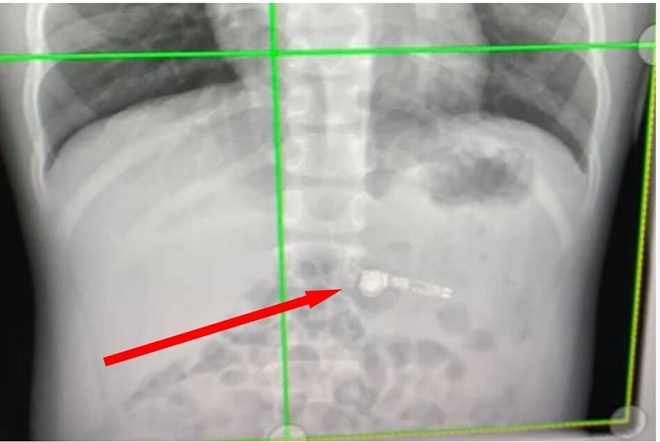

아이 엄마의 가장 큰 걱정은 어떻게 이 기기를 몸밖으로 나오게 할까 하는 것이었지만, 의사들의 처방은 다른 것이 없었다. 보도에 따르면 의사들은 별다른 과정을 사용하지 않았고 "결국 에어팟이 스스로 빠져 나오게 될 것"이라며 가족들을 안심시켰다.